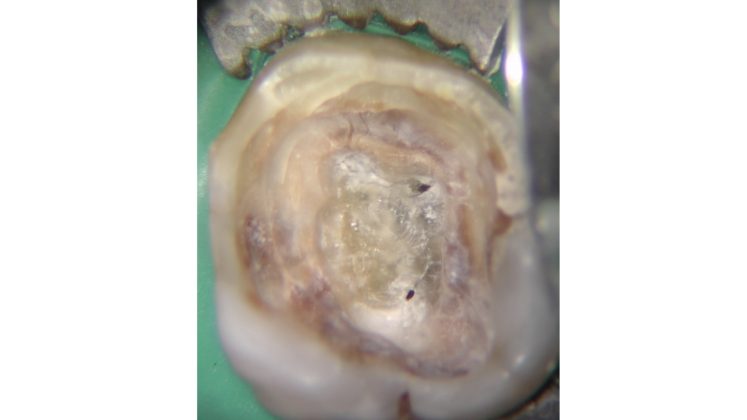

La regola dell'opalescenza e della traslucenza entra in gioco in casi di calcificazioni camerali, situazioni in cui distinguere il pavimento della camera pulpare dalla presenza di residui calcoli può risultare complesso. Iniziare a sondare con strumenti a mano o meccanici un canale prima di aver rimosso tutte le calcificazioni camerali può determinare diversi rischi: complesso inserimento degli strumenti che sarebbero anche sottoposti a un maggiore stress durante la loro attivazione, disseminazione di frammenti all’interno dei canali che potrebbero ostruirsi a diversi livelli.

In aiuto dell’operatore la differente capacità di riflettere la luce (l’utilizzo di una sorgente luminosa assieme al sistema ingrandente agevola molto nella valutazione) del pavimento rispetto al tessuto calcificato risulta un prezioso riferimento.

Il pavimento della camera pulpare si presenta sempre con un aspetto più scuro ed opaco rispetto al tessuto calcificato che tende ad essere lucido con un effetto che potremmo definire “vetrificato” (Figure 15-20).

Talvolta la differenza è evidente, in altri casi molto più sottile e quindi anche le difficoltà incontrate possono essere maggiori.

Non appena vengono identificati gli orifizi canalari la tentazione alla quale resistere è di provare a sondare immediatamente i canali esponendosi ai sopracitati rischi.

Asciugare la camera pulpare è il primo passaggio da compiere per poter visualizzare in modo netto le differenze.

A seguire l’utilizzo alternato di vari dispositivi a secco a bassi giri permette di distaccare ed eliminare i residui calcificati.